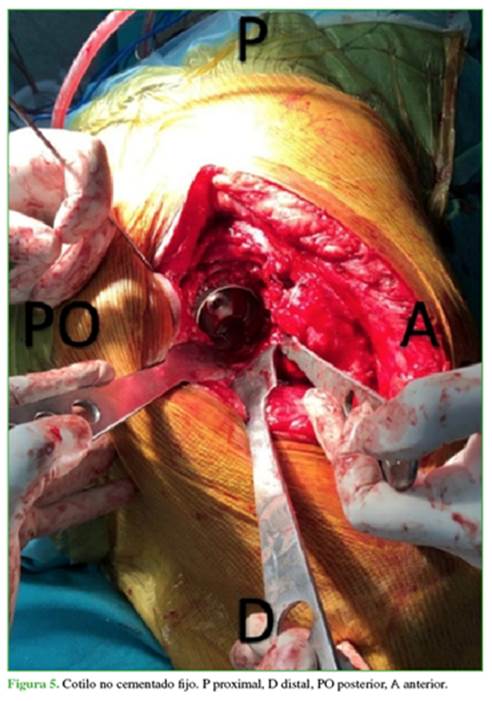

Con la paciente bajo anestesia raquídea en decúbito lateral izquierdo estricto, mediante abordaje posterolateral de cadera se accede hasta el plano protésico y se encuentra luxado el implante; se retira el módulo proximal del componente femoral, para aumento del campo de trabajo, se constata intraoperatoriamente la consolidación del trocánter mayor, dado que radiológicamente impresionaba pseudoartrosis. Se extrae el polietileno del componente acetabular, verificando la correcta orientación y estabilidad del cotilo no cementado anteriormente implantado (Figura 5) y se retiran los tornillos de la copa, para usar los orificios como retenciones para el cementado. Debido al acabado liso de la superficie interna de la cubierta metálica retenida, realizamos rugosidades con una mecha de carburo de tungsteno, lo que aumenta la resistencia a la fijación cementada hasta en un 20%.13 Para evitar que queden desechos metálicos en la articulación, se realizó la cobertura de la zona con gasas y posterior lavado profuso.